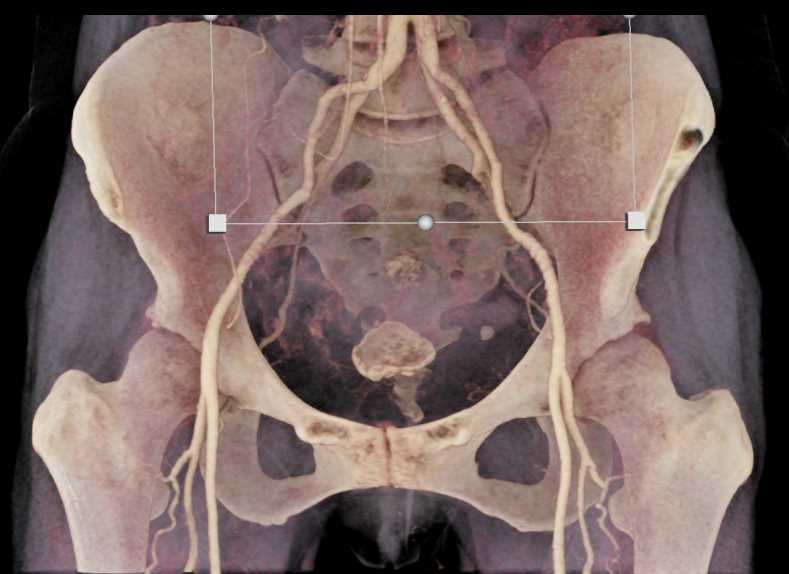

Urachal Carcinoma of the Bladder